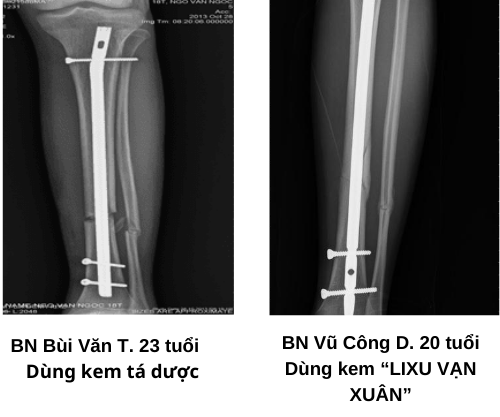

Qua nghiên cứu, cho thấy sau 4 tuần điều trị lô bôi cream LIXU VẠN XUÂN đã có 13,33% đã can xương độ 2, 66,67% đã can xương độ 1, chỉ có 20% chưa can xương. Còn lô chứng không có trường hợp nào can xương độ 2, chỉ có 20% can xương độ 1, đa phần chưa can xương chiếm 80% (bảng 3, hình 7).

Hình 7: Can xương của bệnh nhân sau 4 tuần điều trị

Nhìn vào bảng 4 ta thấy, lô bôi cream LIXU VẠN XUÂN đã có 53,33% can xương độ 2, 46,67% can xương độ 1. Trong khi đó, lô chứng mới chỉ có 23,33% can xương độ 2, 23.33% can xương độ 1 và tới 53,33% chưa có can xương.

Bảng 4: Mức độ can xương sau 8 tuần điều trị

Vậy chứng tỏ bôi cream LIXU VẠN XUÂN giúp can xương nhanh hơn, tức có tác dụng nhanh liền xương trên thực nghiệm lâm sàng.